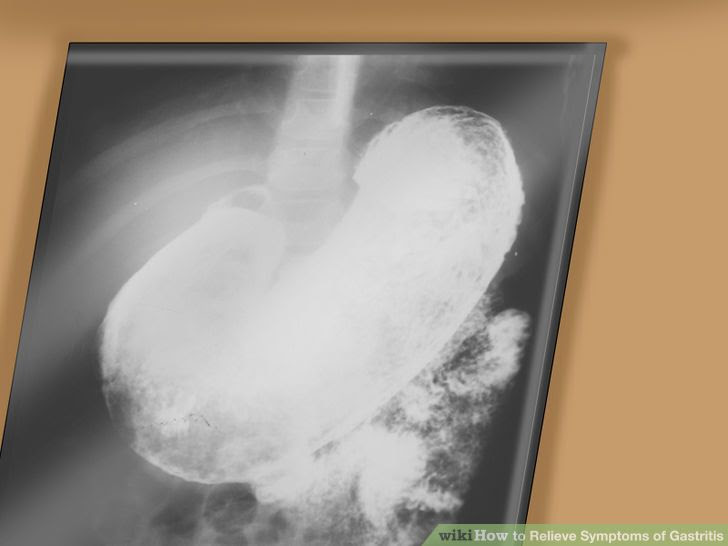

• An x-ray. During this test you will drink white liquid containing barium. The barium coats your esophagus, stomach, and intestines, making them easier to see on the X-ray. This allows your doctor to look for areas with problems.